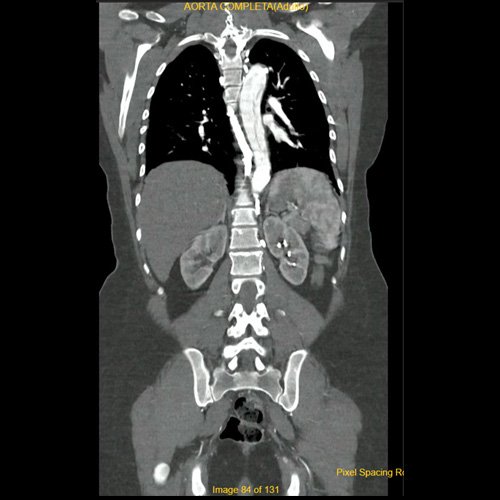

• Angio-TCMS de aorta toracoabdominal y vasos iliofemorales - pre informe (día 0): Interpretación: Se identifica un flap de disección aórtica, que se extiende desde la raíz aórtica, hasta el segmento distal de la aorta torácica descendente, asociado a dilatación aneurismática de la raíz aórtica y la aorta ascendente. No se observa disección de aorta abdominal al momento del examen. El flap de disección compromete la aorta ascendente, el arco aórtico y los tres vasos supraaórticos, extendiéndose hacia el tronco braquiocefálico derecho, con compromiso de la arteria subclavia derecha, así como también de la porción proximal de la arteria carótida primitiva izquierda y de la arteria subclavia izquierda. No impresiona compromiso de la emergencia de las arterias coronarias por esta metodología. Diámetros de la Aorta en sus diferentes porciones:  Senos de Valsalva: 40 mm.  Región media de aorta ascendente: 37 mm. Región media del cayado: 23 mm. Región media de la aorta descendente: 22 mm. A nivel de las cruras diafragmáticas: 19 mm. A nivel del origen del tronco celíaco: 18 mm. A nivel infrarrenal: 14 mm. Previo a su bifurcación iliaca: 13 mm. Hipertrofia del ventrículo izquierdo. Derrame pericárdico de 13 mm de espesor a nivel de cara anterior, de densidad promedio de 30 UH. El esófago es de calibre y trayecto normales. El mediastino está en posición central. No se observan adenomegalias mediastinales, axilares o hiliares. El árbol traqueobronquial no presenta alteraciones. Áreas de aneumatosis bibasal. No se observa derrame pleural. El hígado es de forma, tamaño y situación habituales. Su superficie es lisa, y sus bordes son agudos. El parénquima hepático presenta atenuación heterogénea, con áreas hipodensas difusas, hallazgos que podrían estar en relación con trastorno perfusional. Se observa además edema periportal. La vía biliar intra y extrahepática es de calibre conservado. La vesícula biliar es de forma, tamaño y situación normales, sin imágenes que sugieran la presencia de litiasis. Tener en cuenta que este método puede pasar por alto litiasis colesterínicas. Edema perivesicular. El bazo es de forma, tamaño y situación normales. El eje esplenoportal es de calibre y trayecto conservado, permeable. El páncreas es de características normales. El conducto de Wirsung es de calibre conservado. Las glándulas adrenales son normales. Ambos riñones son de forma, tamaño y situación habituales. Concentran y eliminan normalmente la sustancia de contraste, sin evidencia de alteraciones calicopiélicas ni ureterales. La vena cava inferior y las venas ilíacas primitivas, internas, externas y femorales son de calibre y trayecto conservados, permeables. No se observan adenomegalias intraperitoneales, retroperitoneales, ilíacas ni inguinales. No se observan alteraciones a nivel del tracto gastrointestinal. Vejiga con escasa repleción, con sonda balón en su interior. El útero es de forma, tamaño y situación conservada, sin alteraciones densitométricas, en anteversoflexión. En topografía de ambos anexos se observan colecciones líquidas de aspecto funcional que miden 23 mm a izquierda y 18 mm a derecha. Escasa cantidad de líquido libre en el fondo de saco de Douglas. Espondiloartrosis de la columna dorso-lumbar.

A su ingreso, se realiza interconsulta a servicio de Clínica Médica. Por sospecha de aneurisma de aorta y debido a cuadro clínico actual, se solicita angiotomografía de aorta torácica y abdominal.  En dicho estudio se evidencia disección aórtica Stanford tipo A con compromiso hasta territorio torácico, por lo que se decide su pase a Unidad Coronaria para monitoreo contínuo. Inició tratamiento médico antihipertensivo con nitroglicerina endovenosa.

Angiotomografía con contraste endovenoso de aorta toracoabdominal. Corte coronal.